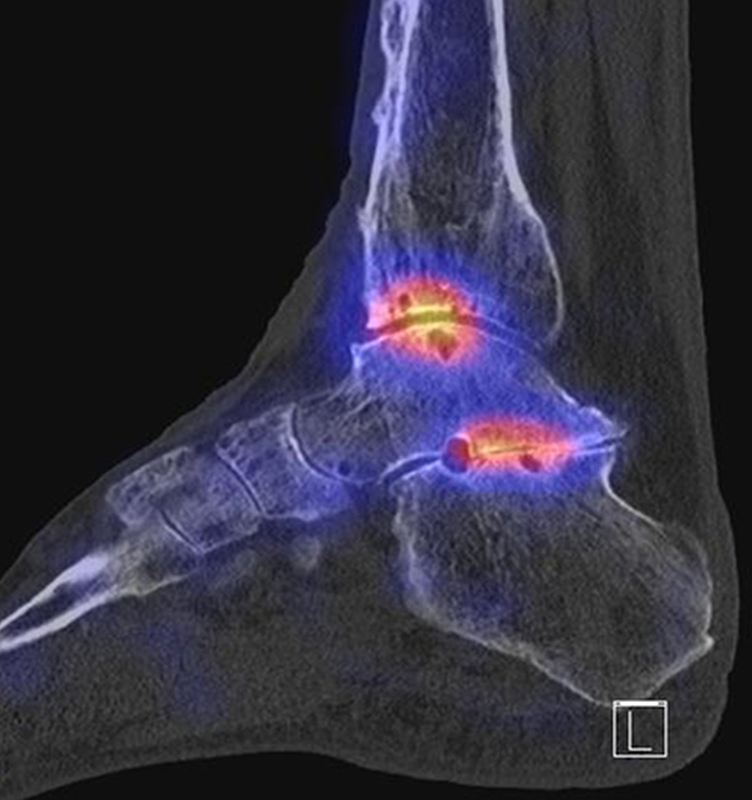

SPECT/CT zur Beurteilung von Arthrodesen

Arthrodesen gehören seit langem zu den Standardverfahren bei Fehlstellungen oder schmerzhaften Arthrosen 4546 (Graves, 2000). Eine zumindest teilweise knöcherne Durchbauung von Arthrodesen sollte in der Regel innerhalb von 6 Monaten nach der OP nachweisbar sein 647. Eine unvollständige oder fehlende Fusion nach Arthrodese kann permanente Schmerzen verursachen, was sich mit der SPECT/CT nachweisen lässt. Abbildung 5.1. zeigt den Fall eines Patienten mit persistierenden Beschwerden 1 Jahr nach calcaneo-cuboidaler Arthrodese, es besteht ein erhöhter Knochenmetabolismus im Bereich der Arthrodese bei teilweise noch abgrenzbarem Gelenkspalt; kein Nachweis von Anschlussarthrosen in den benachbarten Gelenken. Persistierende Beschwerden nach Arthrodese können jedoch auch durch Überlastungen angrenzender Gelenke entstehen, die dann in Arthrosen münden 48. Ein entsprechendes Beispiel ist in Abbildung 5.2. dargestellt, die den Verlauf bei einer Patientin mit Z. n. Arthrodese wegen einer talonavicularen Arthrose zeigen.

Ein weiteres Beispiel für eine im Verlauf entstandene symptomatische Arthrose in den Nachbargelenken zeigen die Abbildungen 5.3.a und b. Bei dem Patienten bestand ein Z. n. subtalarer und talo-navikularer Arthrodese vor 11 Monaten mit Beschwerden beim Abrollen im linken Sprunggelenk mit dem Gefühl „einer Sperre“. Abbildung 5.3.b zeigt die Entwicklung einer anterior betonten hypermetabolen OSG-Arthrose mit Zeichen einer teilweise knöchernen Durchbauung der subtalaren Arthrodese links. Noch keine signifikante Durchbauung der talo-navikularen Arthrodese links. Die Abbildungen 5.4.a bis c zeigen als Erklärung für Schmerzen eine symptomatische Osteochondrale Läsion in der Talusrolle bei knöcherner und reizloser Durchbauung der Arthrodesen 14 Monate nach USG- und TN-Arthrodese.

Der optimale Zeitpunkt einer Evaluation bei Verdacht auf eine symptomatische Arthrodese ist nicht definiert. Im Rahmen einer prospektiven Studie an 30 Patienten mit 31 Sprunggelenksarthrodesen wurden diese prä- und 6 Monate postoperativ mit SPECT/CT und klinisch zusätzlich mit standardisierten Fragebögen (Ankle Osteoarthritis Scale (AOS), 36-item Short Form Survey (SF-36), Physical component score (PCS) and mental component score (MCS)) untersucht 49. Der klinische Erfolg war durch eine Schmerzreduktion unter Belastung definiert (bei 87 %). Radiologisch wurde eine knöcherne Durchbauung von ≥ 50 % nach 6 Monaten als Erfolg definiert (bei 71 %). Szintigraphisch wurde sowohl der Metabolismus um das fusionierte obere Sprunggelenk als auch um die Talonavicular- und Subtalar-Gelenke gemessen. Die Metabolismus um die OSG-Arthrodese war vom präoperativen nicht signifikant verschieden, wobei der Metabolismus um die Talonavicular- und Subtalar-Gelenke signifikant zunahm.

Diese Ergebnisse unterscheiden sich von den zahlreichen präoperativen Studien, die eine hohe Korrelation zwischen SPECT/CT-Metabolismus und klinischen Beschwerden zeigen. Der Grund liegt darin, dass die Szintigraphie sehr sensitiv die Aktivität von Osteoblasten anzeigt und nach 6 Monaten die knöcherne Durchbauung im Sinne einer Normalisierung des Knochenstoffwechsels noch nicht abgeschlossen ist. Unter diesem Aspekt erscheinen 6 Monate zu früh für eine szintigraphische Arthrodesen-Beurteilung.

Der zunehmende Metabolismus in den Talonavicular- und Subtalar-Gelenken ging nicht mit morphologischen Veränderungen als Hinweis auf Anschluss-Arthrosen her, so dass die Autoren diese Befunde als belastungsbedingt bzw. reaktiv nach OP einstuften; wohlgemerkt hatten die Patienten ja weit überwiegend eine deutliche klinische Besserung nach der OSG-Arthrodese erfahren 49.